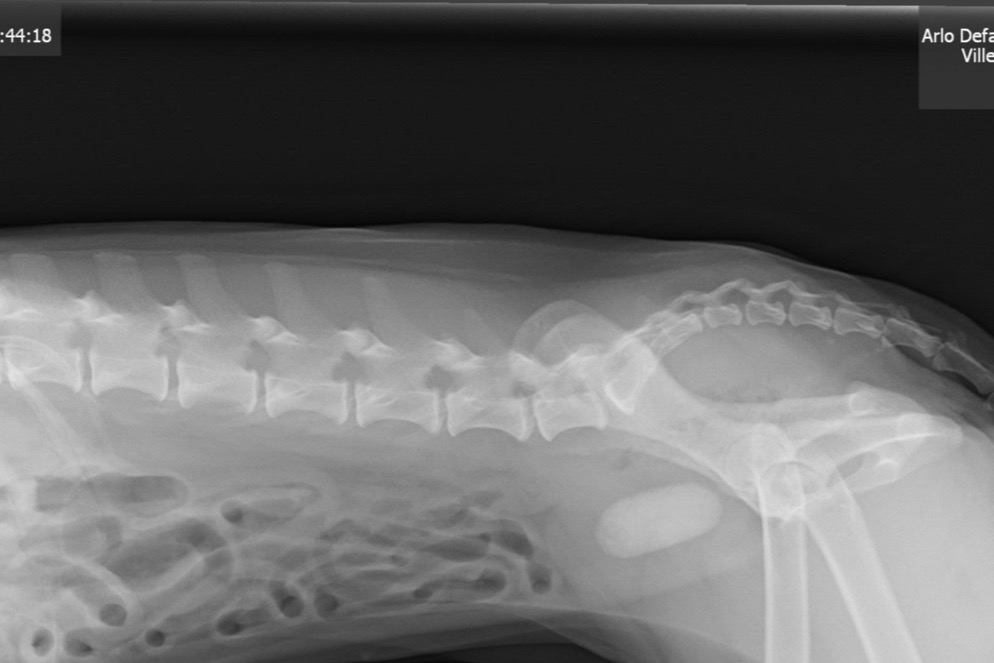

Arloe is a rescue dog that my daughter adopted in 2016. In the last few weeks, she has been having trouble urinating, and I assumed it was a urinary tract infection. I took her to the veterinarian today and found out we are not so lucky. Arloe, who is just over 10 lbs, has a huge bladder stone.

You can see the bladder stone clearly in the X-ray, and I have included the estimate as well. Both done this afternoon.